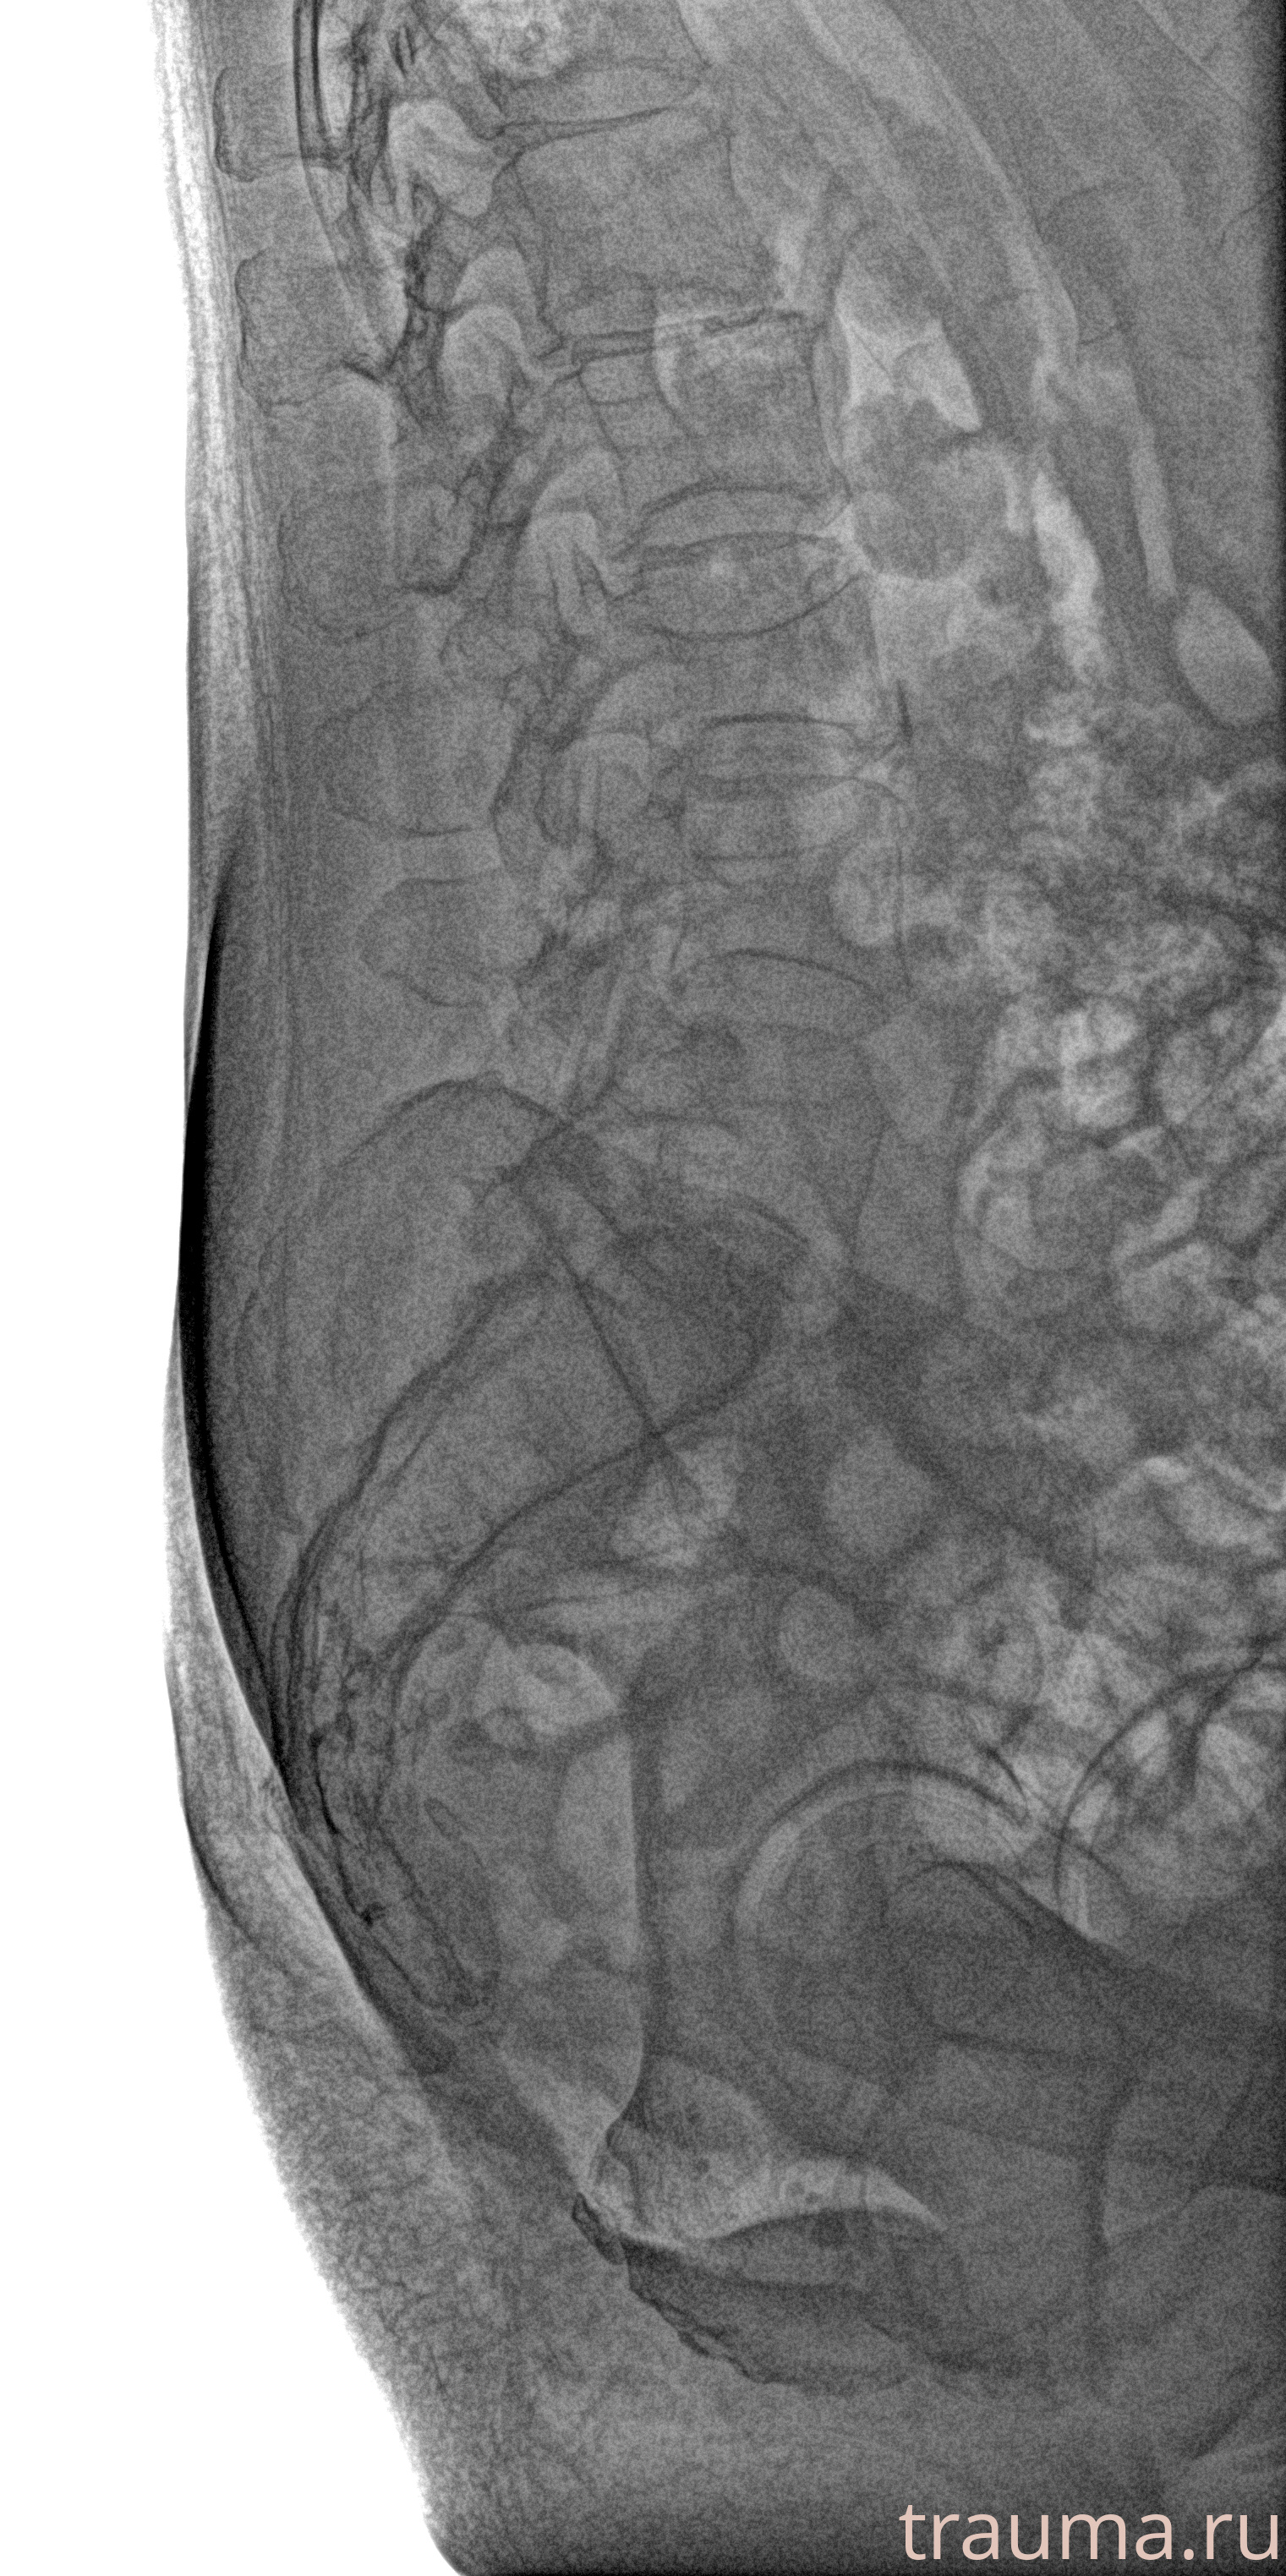

Рентген на дому: по вашему адресу приезжает врач-рентгенолог, травматолог-ортопед с мобильным рентгеновским аппаратом, проводит диагностику травмы или заболевания, делает необходимые рентгенограммы, дает рекомендации по дальнейшему лечению. Получить качественные снимки в домашних условиях возможно благодаря уникальной методике, разработанной МосРентген Центром для института  Склифосовского